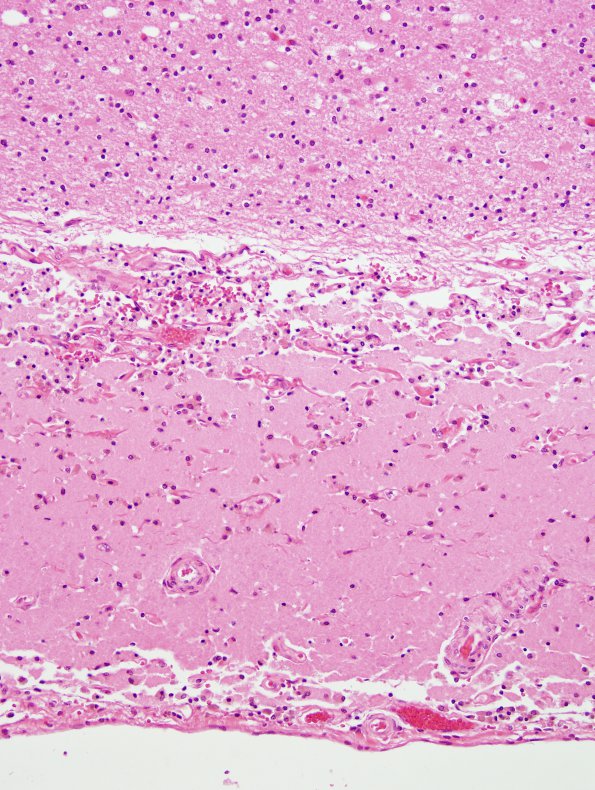

1C3 Laminar necrosis (Case 1) N19 H&E 5

Higher magnification of the gray white junction seen in image 1C2 (H&E)